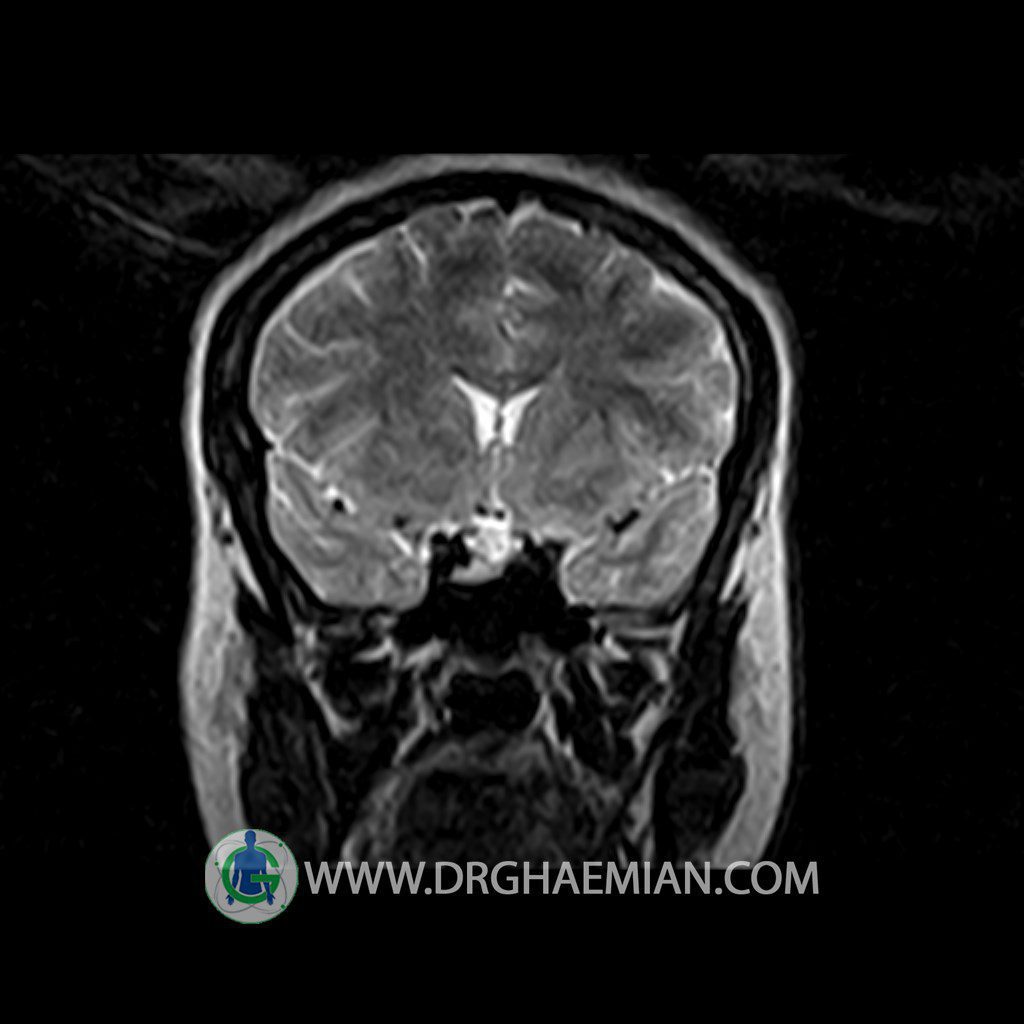

ام آر آی هیپوفیز یک روش تصویر برداری است که از غده هیپوفیز (غده ایی کوچک در مغز که هرومون ها و دیگر غدد بدن را کنترل می کند) و ناحیه های پیرامونش در مغز تصاویری ایجاد می کند. در این کیس سلای نسبتا خالی در ناحیه هیپوفیز بیمار مشاهده می شود.

HYPOPHYSIS MRI

(with and without contrast)

Technique: Axial , coronal T1 , Axial , coronal , sagittal T2 , Axial, coronal T1 post Gd & 64 dynamic thin coronal slices.

REPORT :

The pituitary tissue shows normal , position, shape , size and homogeneous signal intensity both before and after contrast administration .

Anterior and posterior pituitary gland were normal .

It contains no circumscribed hypointense or hyperintense areas .

The infundibulum is centered and of normal size .

The optic chiasm and suprasellar spaces appear normal .

The cavernous sinus and imaged portions of the internal carotid artery and carotid siphon are unremarkable .

Evaluable portions of the neurocranium show no abnormalities .

The sphenoid sinus is clear and pneumatized .

Imaging of the hypothalamus after contrast medium administration was normal.

– Extension of suprasella cistern to sella with thin pituitary gland in floor of sella ( partial empty sella )

is seen